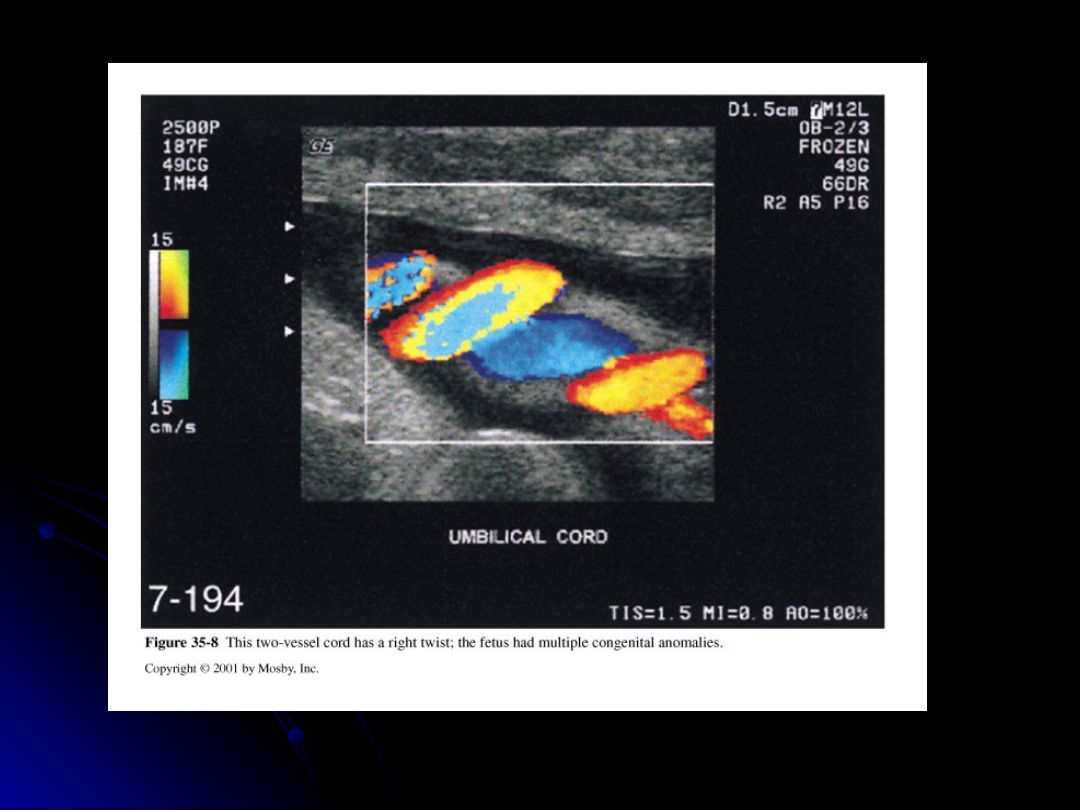

Which of the following statements about the twists of the umbilical cord are correct?

Cord can coil up to 40 times due to fetal movement.

A left helix is more common than a right helix.

Multiple Choice

What is the clinical significance of a 'right' twist in the umbilical cord?

It is associated with a higher incidence of fetal anomalies.